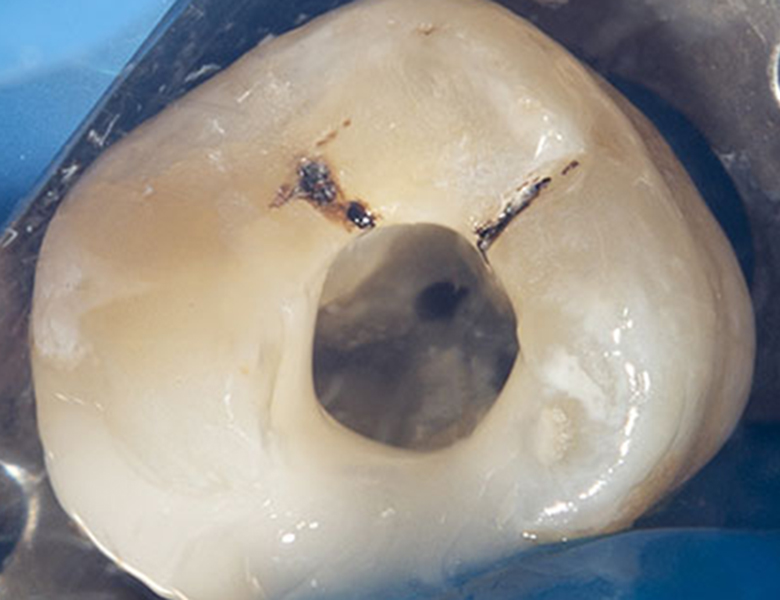

マイクロスコープで見ている世界(最大20倍以上)

肉眼の約20倍の世界では、歯の表面にある目に見えない小さな亀裂、古い詰め物のわずかな段差、複雑に枝分かれした根管(歯の神経の通り道)の隅々までが、まるで明るい昼間に映画のスクリーンを見ているかのように鮮明に映し出されます。

1ミリ以下の精密な除去

マイクロスコープを使用すれば、虫歯に侵された組織と、温存できる健康な組織の境界が鮮明に見えます。

健康な部分を1ミリも無駄にせず、感染部位だけを精密に除去することで、従来は諦めていた神経を残せる可能性が飛躍的に高まります。